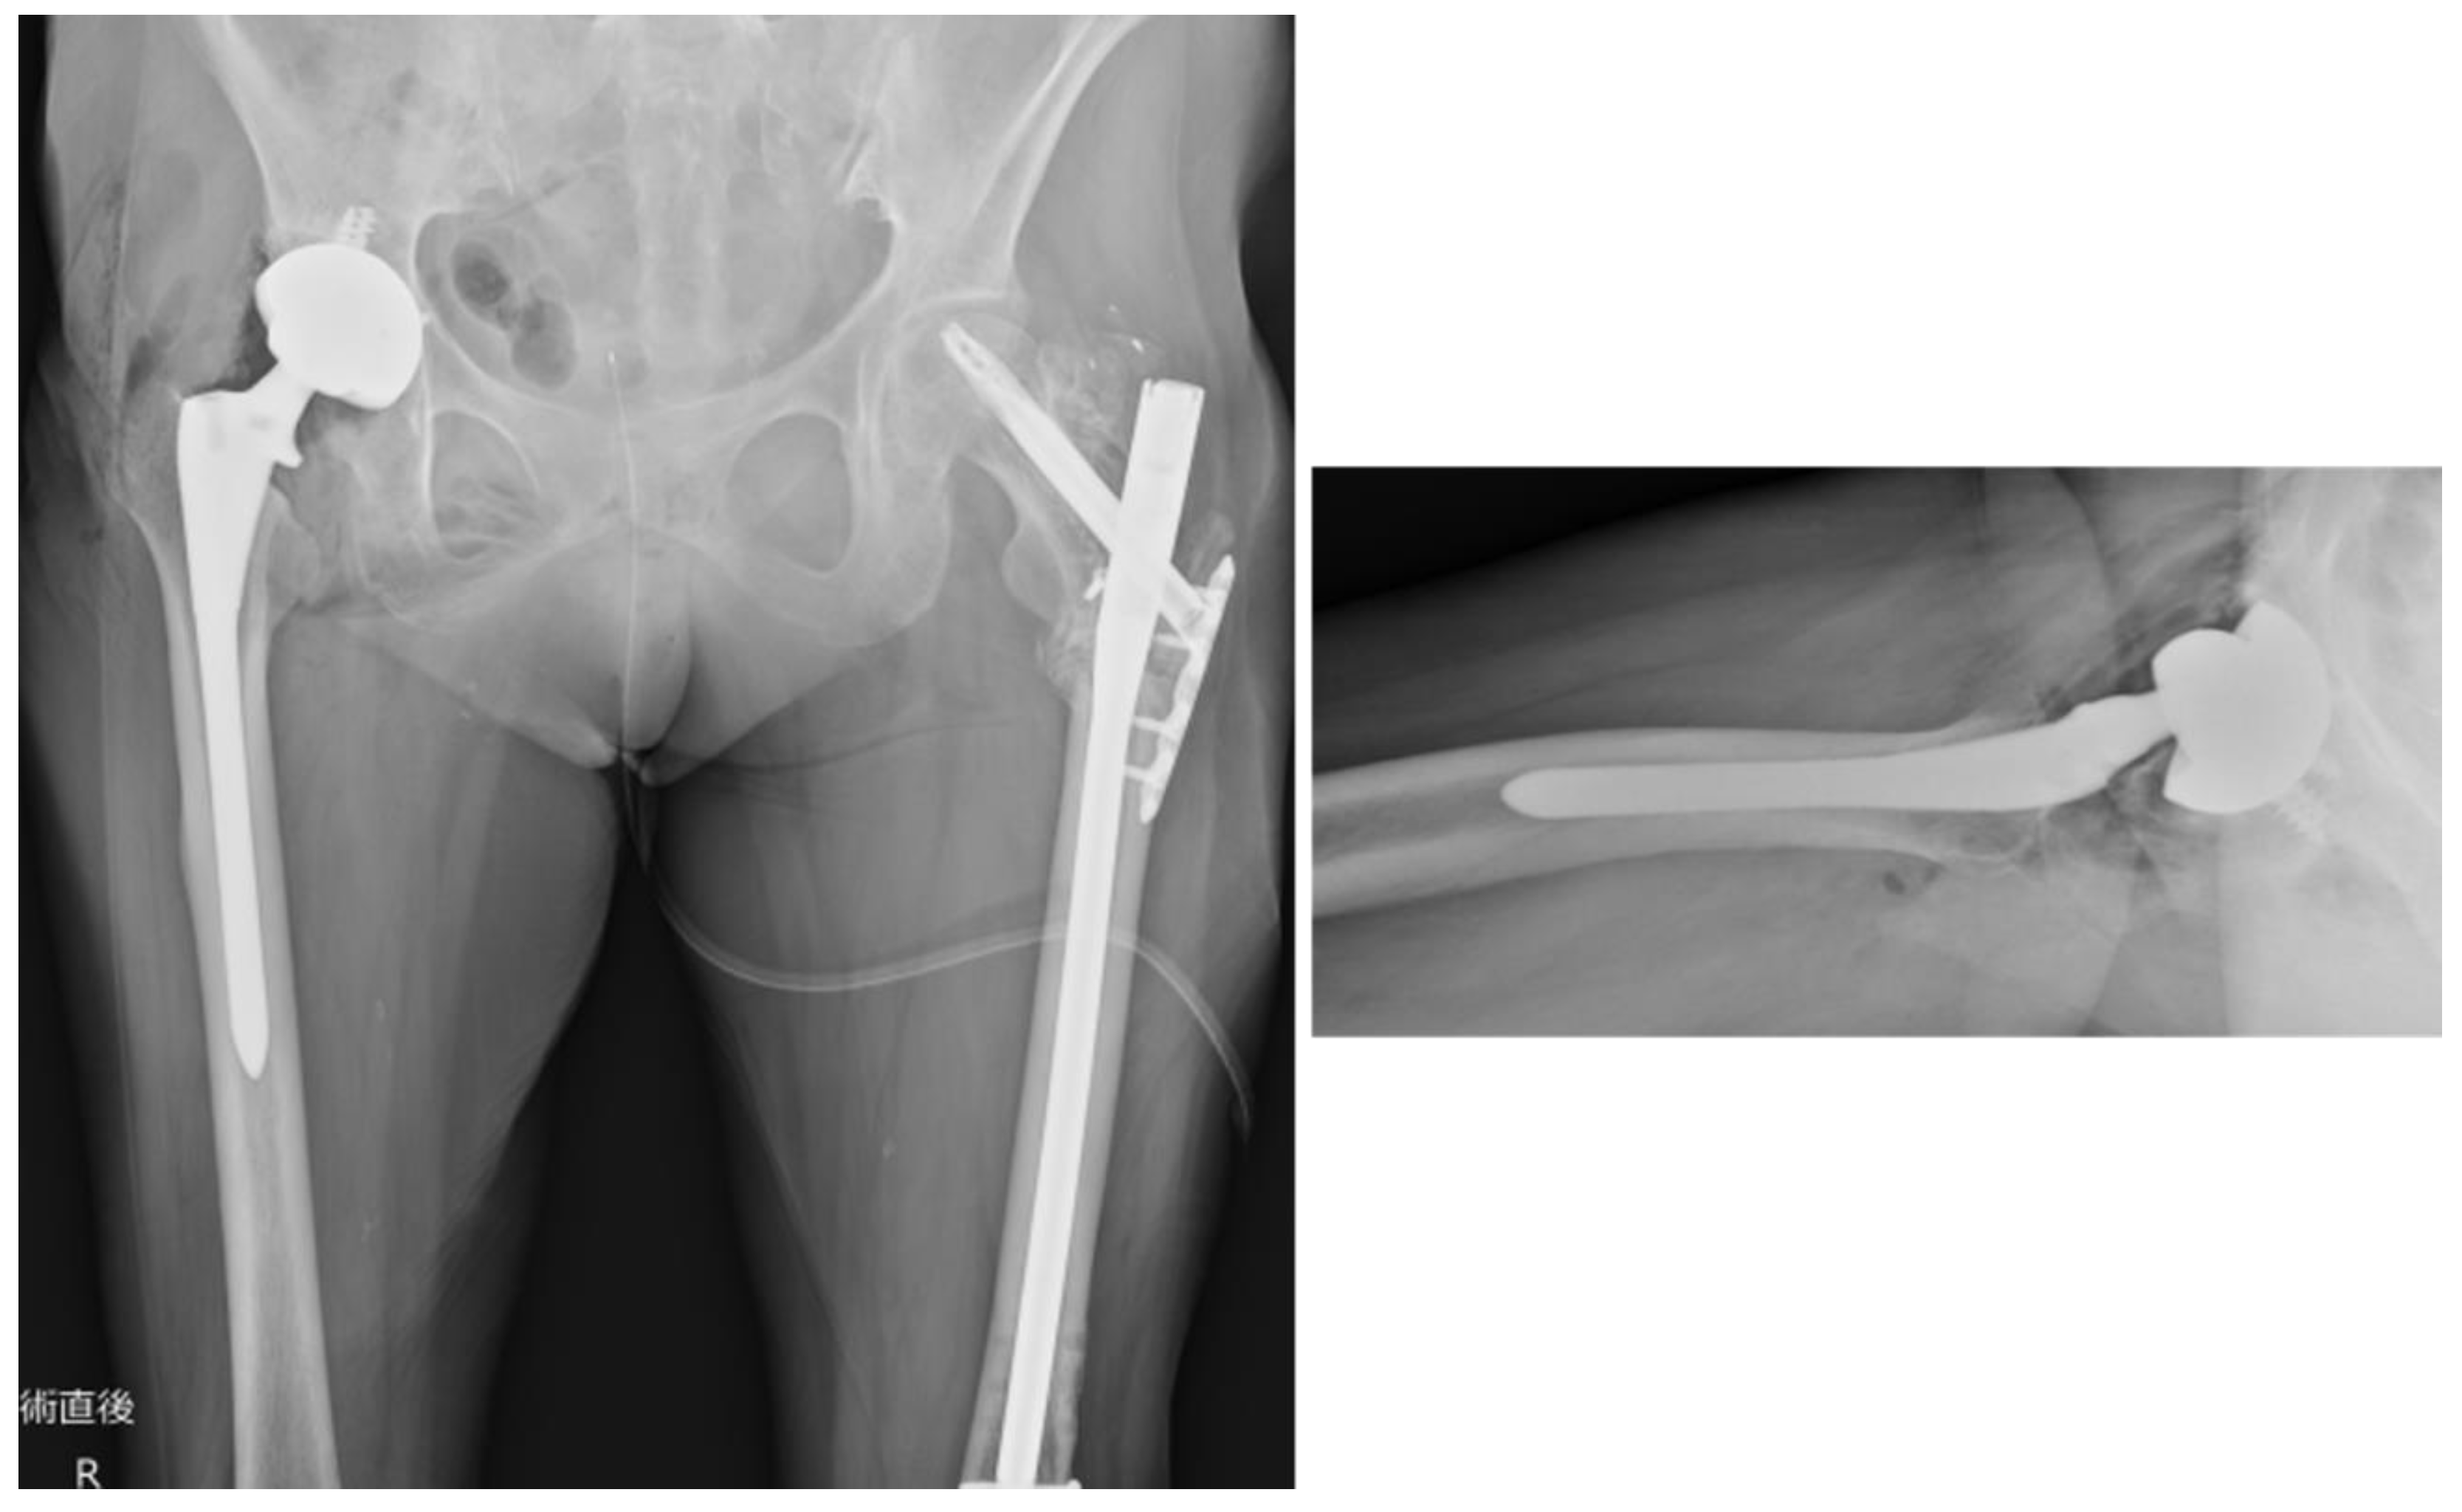

Based on the abovementioned findings, we performed THA using a posterior approach (Figure 9). Postoperatively, full weight bearing on the affected limb was allowed. The patient could walk with a cane and was transferred to another hospital for rehabilitation on postoperative day 14. At the final follow-up (3 months postoperatively), the patient could walk independently and experienced no difficulties in daily activities.

Figure 9. Plain radiograph of the hip joint immediately postoperatively. The stem (Arcos® One-piece Femoral Revision System, Zimmer, Warsaw, Indiana, USA, φ9.5 mm × 175 mm, high offset) was inserted to a depth of 11 mm below the apex of the greater trochanter, as planned preoperatively. The cup (Continuum®, Zimmer, Warsaw, Indiana, USA, Φ28/46 mm) was fixed and positioned using four screws. The surgery was completed in 1 h 20 min, with a blood loss of 50 ml.